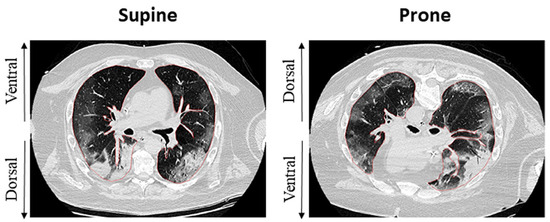

Chang et al. [100] assessed the association of biomarkers with mortality. They established baseline, 24 h, and 72 h measurements. They assessed mortality at 14 and 28 days after the initiation of mechanical ventilation. In this study, IL-6 was shown to be a predictor of mortality at 14 days in both supine and prone patients, while it was not shown to be a predictor of mortality at 28 days. To this date, data are lacking regarding the predictive ability of biomarkers in the prone position in terms of the duration of mechanical ventilation or ICU stay (Figure 3).

Figure 3.

A schematic figure of clinically relevant biomarkers in supine and prone positions during ARDS. See the text for details.